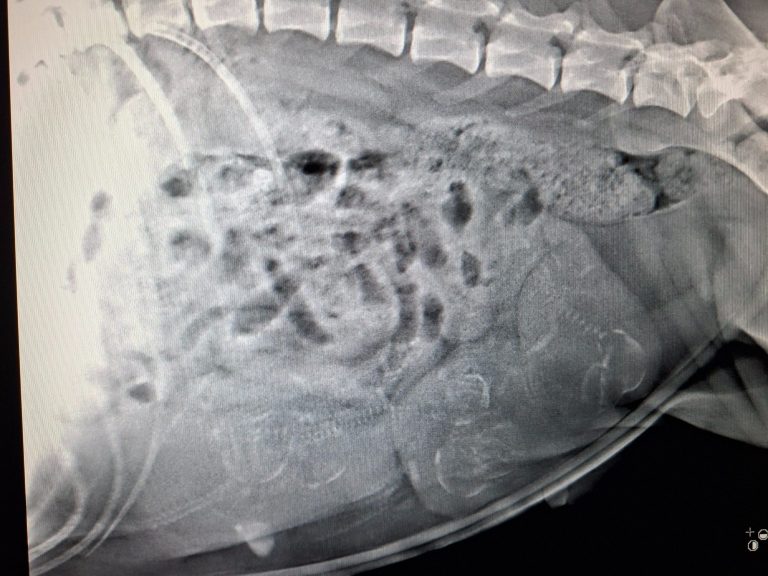

Heute hatten wir unseren Termin beim Tierarzt und es wurde geröntgt. Leider ist das Bild nicht so wirklich aussagekräftig geworden. Obwohl ich mit Kuba vorher noch ausgiebig draußen gewesen bin, ist der Darm leider doch noch zu voll gewesen. Daher ist der größte Teil mit einem vollen Darm überlagert und zählen war nicht wirklich möglich.

Sie für diesen Termin hungern zu lassen ist für mich aber nicht in Frage gekommen. Das Risiko, dass es ihr und den Welpen deswegen danach schlecht geht, ist es nicht wert. Ich hätte mir ein genaueres Bild gewünscht aber wichtiger ist es, dass es allen gutgeht.

Die kleinen Knöchelchen sind am 53. Tag auch noch nicht sehr gut darstellbar. Naja so ist es eben. Unser Tierarzt hätte uns noch ein weiteres Röntgen am 57. Tag vorgeschlagen aber ich möchte Kuba weiteren Stress jedoch nicht mehr zumuten. Wir warten jetzt einfach ab und lassen uns überraschen.